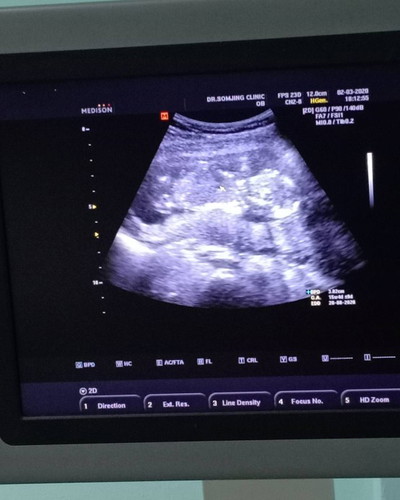

น้องหนีบขาไว้ค่ะ แต่หมอบอกน่าจะเป็นผู้หญิง แม่ดีใจมาก จะได้ลูกสาว แต่ก็รอลุ้นเดือนหน้าอีก จะมีจู๋รึป่าว ?? โอกาสที่จะเป็นผู้หญิงกี่เปอร์เซ็นค่ะแม่ๆ

VIP Parentsน้องหนีบขาไว้ค่ะ แต่หมอบอกน่าจะเป็นผู้หญิง แม่ดีใจมาก จะได้ลูกสาว แต่ก็รอลุ้นเดือนหน้าอีก จะมีจู๋รึป่าว ?? โอกาสที่จะเป็นผู้หญิงกี่เปอร์เซ็นค่ะแม่ๆ